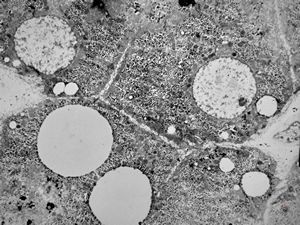

F,1y. | steatosis - Reye hepatocerebral syndrome